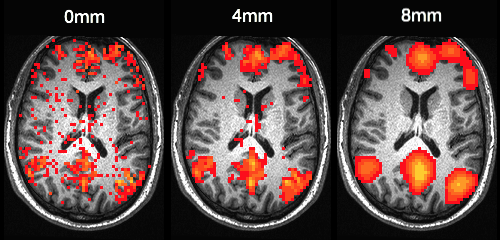

Smoothing is accomplished by applying a Gaussian filter (also known as a kernel) to the original image. This results in the signal of each voxel being replaced by the weighted average of its neighbors (Ashby, 2011). It is the shape of the kernel that defines the weights applied during smoothing. As a Gaussian kernel is essentially a normal distribution, weight is always strongest at the voxel being smoothed and decreases with distance at a rate that depends on the width of the distribution. Wider distributions result in greater smoothing, as more distant voxels recieve higher weights than they would with a thinner kernel. Unlike in statistics, where the width of a distribution is described by the standard deviation, the shape of a smoothing kernel is usually described by the width of the distribution at half of its maximum value. This is known as the Full Width Half Maximum (FWHM). The figure below shows the smoothing effect of different FWHM values.

../_images/smoothing.png